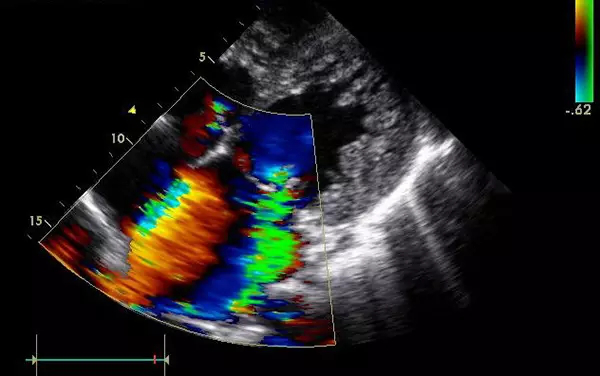

B超

B超的原理是用超聲波穿透人體,當(dāng)聲波遇到人體組織時(shí)會(huì)產(chǎn)生反射波,通過計(jì)算反射波成像。

優(yōu)點(diǎn):多方向觀察,實(shí)時(shí)成像。

缺點(diǎn):超聲受氣體干擾很大,對于腸道等含氣較多的器官,超聲診斷準(zhǔn)確率會(huì)降低,所以一般腸道檢查使用腸鏡。

4、腹部盆腔——除腸道外,一般超聲都能查

5、心臟——排除冠心病用CT,看心功能用超聲